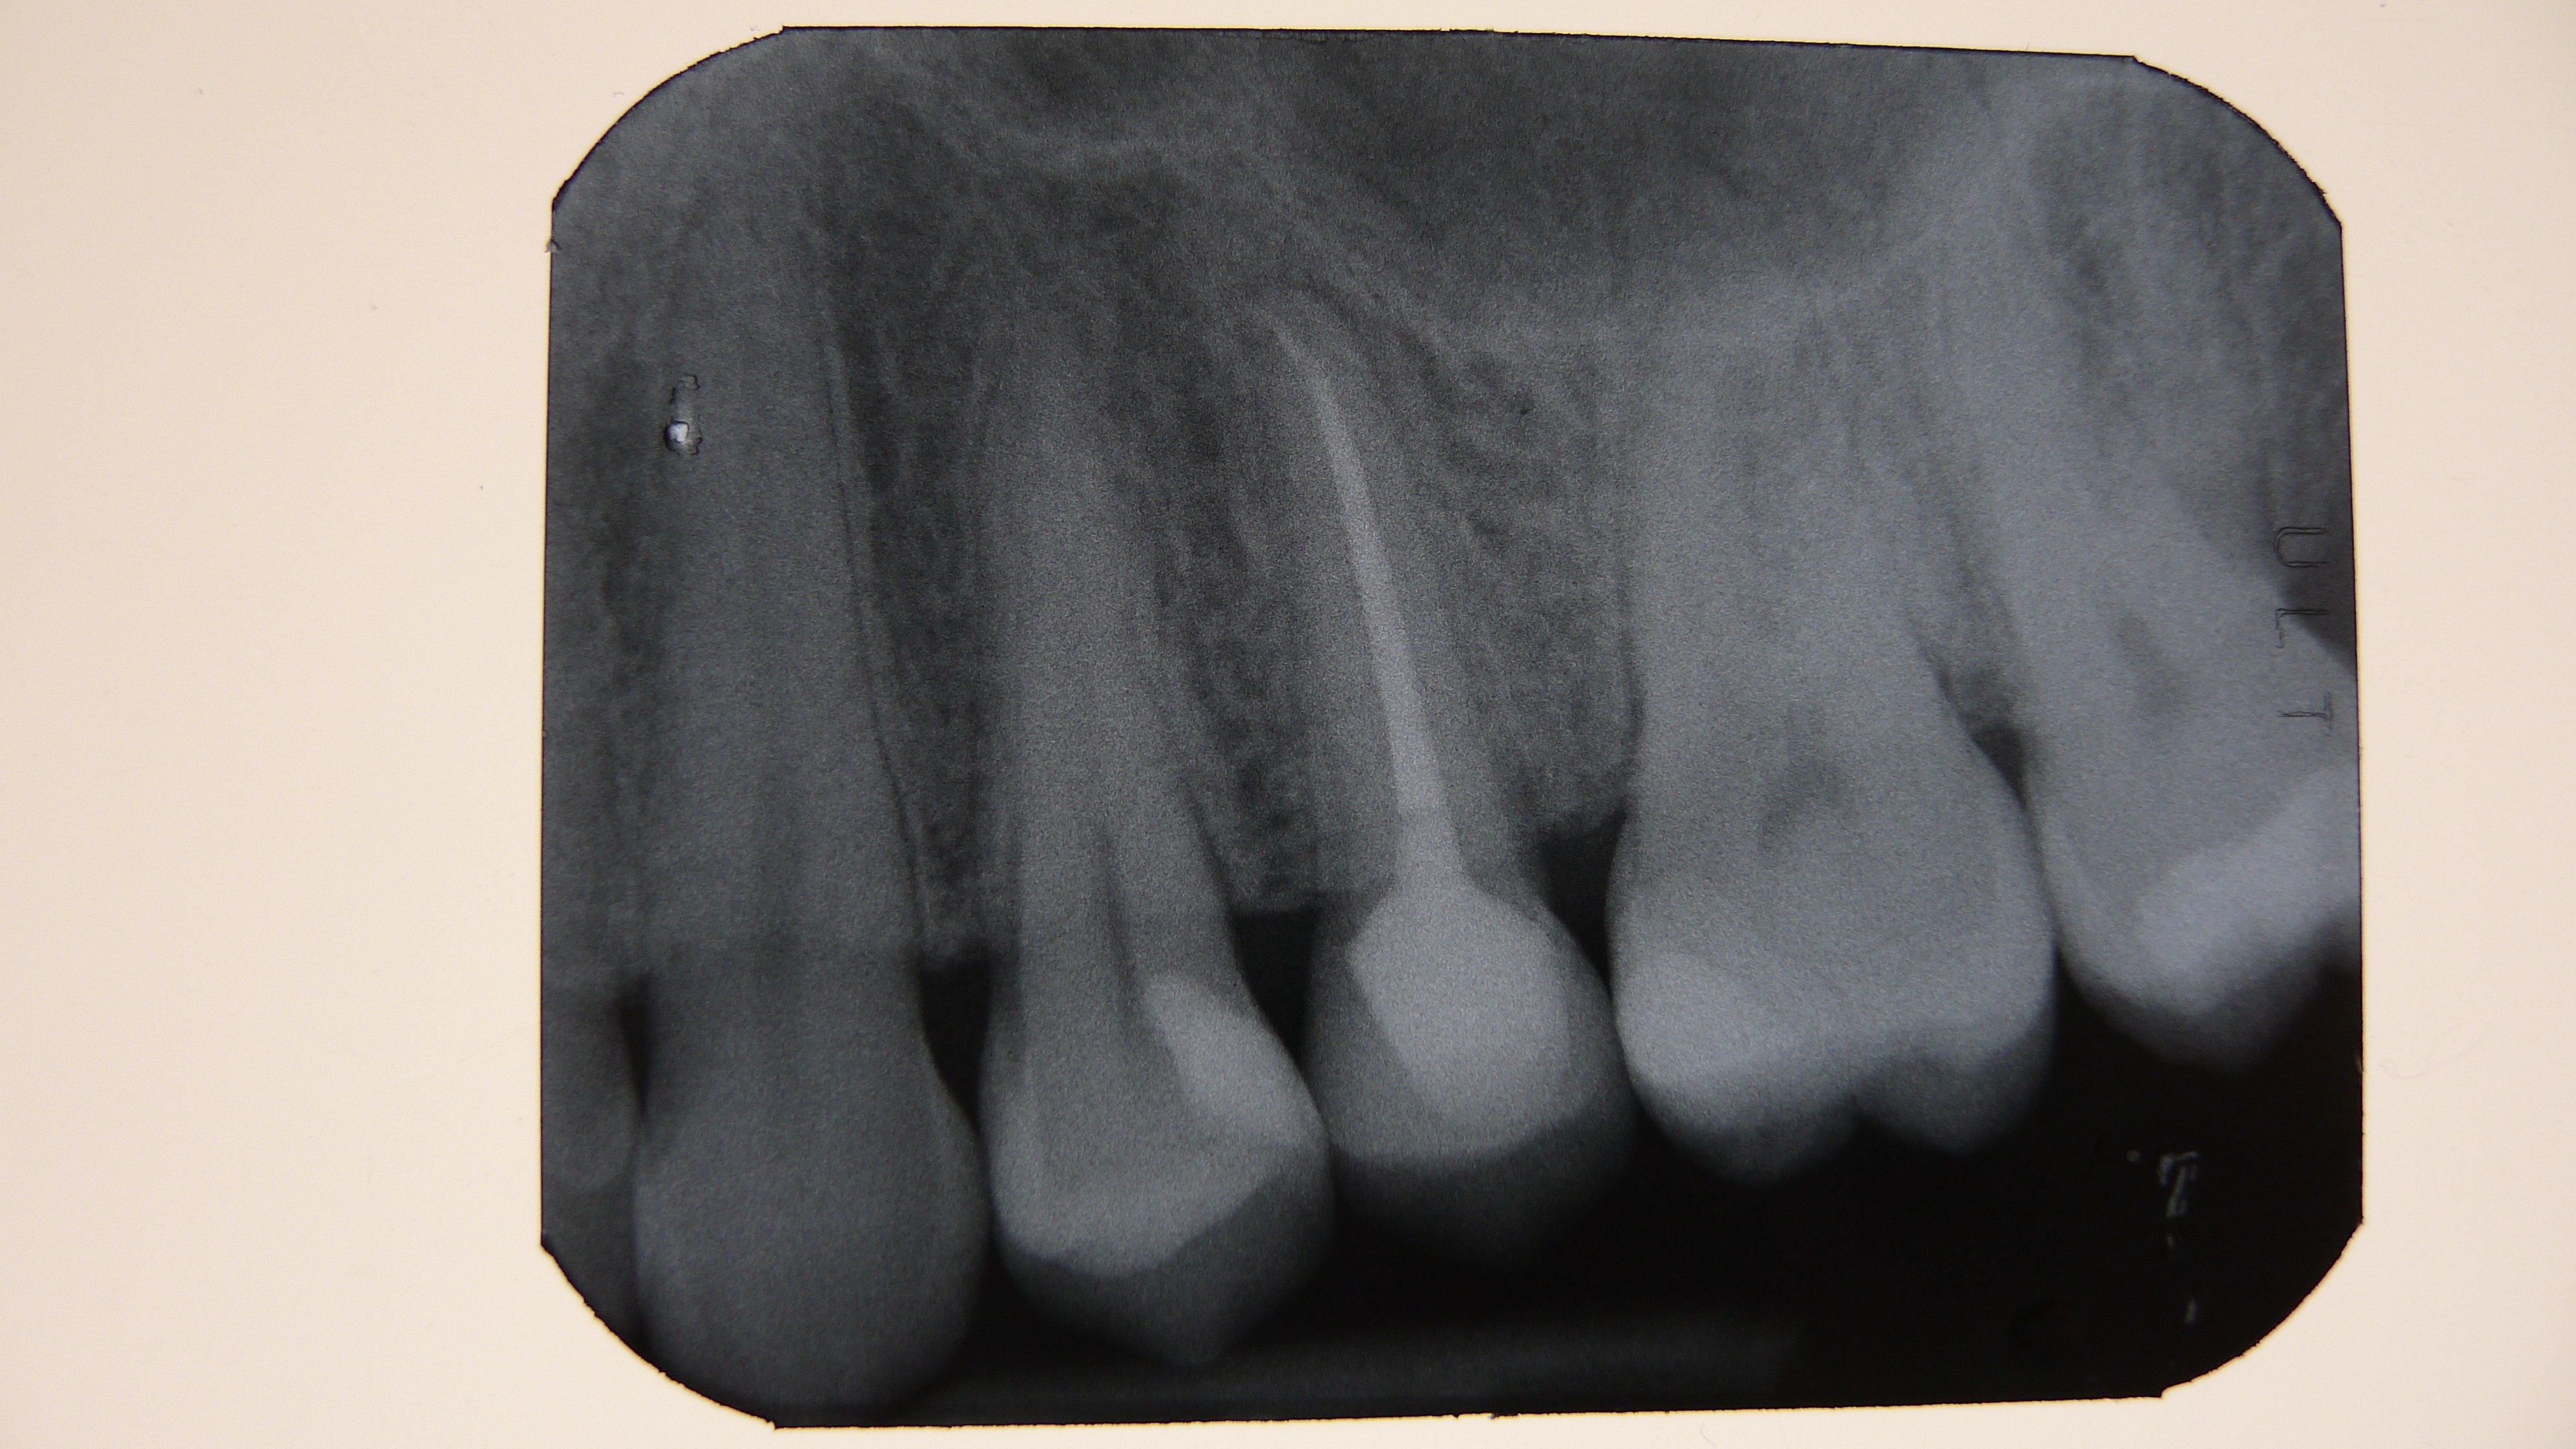

The radiolucent area of the coronal portion of the root is evident, well below the bone crest from the radiographs. I also warned my colleague of the presence of numerous interproximal carious lesions.

Figure 1. Bite Wing X-ray and Apical X-ray of tooth 25 completely compromised by the carious process.Figure 2. Clinical image of tooth 25 totally destroyed at the coronal level.